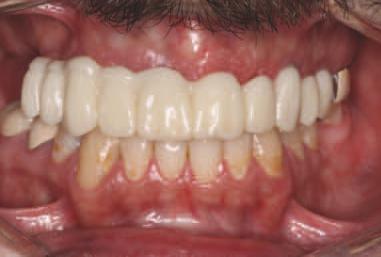

O pac entă de 61 an s-a prezentat la Per odont cs/Per odontal Prosthes s Cl n c d n cadrul Un vers ty of Pennsylvan a School of Dental Med cne dor nd în pr nc pal să a bă „d nț f xaț ” în locul protezelor mob le ex stente (f g. 1). După f nal zarea unu examen stomatolog c cupr nzător, nclus v exam narea extra- ș ntraorală, evaluarea pr n tomograf e computer zată cu fasc cul con c (CBCT), fotograf erea dentară ș întocm rea f șelor dentare, s-a creat un plan pentru real zarea une reab l tăr full-mouth folos nd mplantur ș proteze dentare f xe. Pac enta purta proteze totale moble retenț onate pe m n - mplantur atât la mand bulă, cât ș la max lar. În t mpul evaluăr n ț ale, ea ș -a expr mat preocupăr le legate de estet ca restaurăr lor ex stente în ceea ce pr vește expunerea g ng vală ș

2. Pacienta prezenta expunerea excesivă a componentei gingivale din protezele existente.

3. Situația pretratament mandibulară edentată cu cele patru mini-implanturi existente.

15. Vedere extraorală a restaurărilor finale livrate.

16. Vedere intraorală a restaurărilor finale mandibulare livrate.

În cab net, restaurăr le prov zor au fost deșurubate ș îndepărtate d n cav tatea orală pentru ca restaurăr le f nale să poată f l vrate ș strânse cu un cuplu de 15 Ncm, conform recomandăr producătorulu (f g. 15,16). Ajustăr le ocluzale f nale au fost m n me ș efectuate ntraoral pr ntr-o ultmă lustru re a zonelor ajustate.